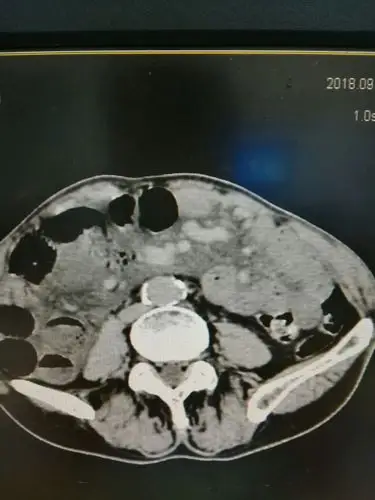

急性肠系膜血管缺血的ct表现及介入治疗

我院ct室诊断首例 高漏诊危急重症病例~~~~肠系膜动脉栓塞